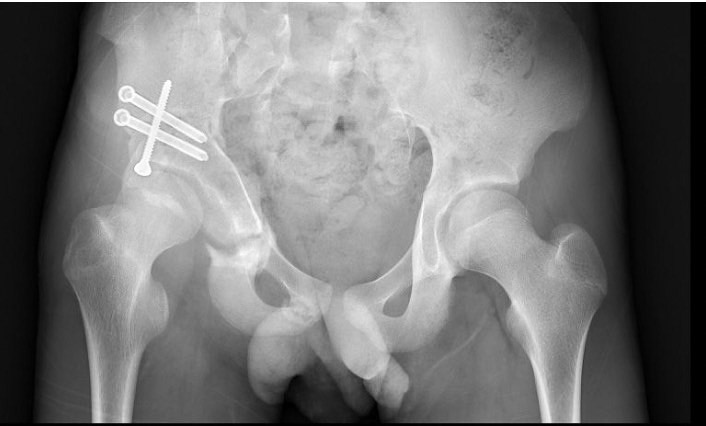

半年過去,父子倆再次來到門診。「髖關節三位截骨矯正手術的意思是我們會將髖骨的前側、後側與上側切割截斷,再將髖骨旋轉矯正至正確位置並用骨釘與石膏固定,這樣就能夠使髖關節活動時的壓力減少,日後走路也可以輕鬆一點。」在手術前一天,黃盟仁醫師仔細解釋整個手術計畫。

經由「髖關節三位截骨矯正手術」,將髖骨旋轉矯正至正確位置。圖/黃盟仁醫師提供